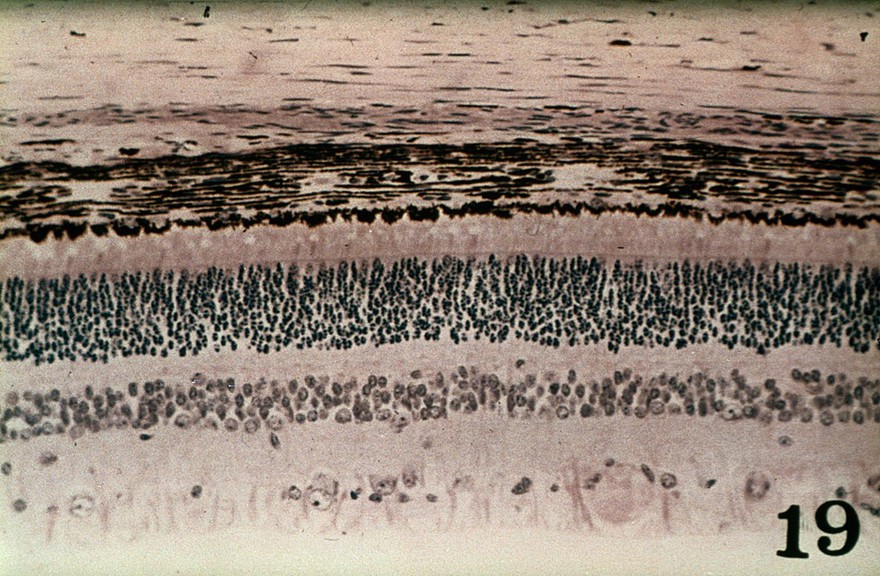

Histological section of the canine retina.

P Bedford/RVC